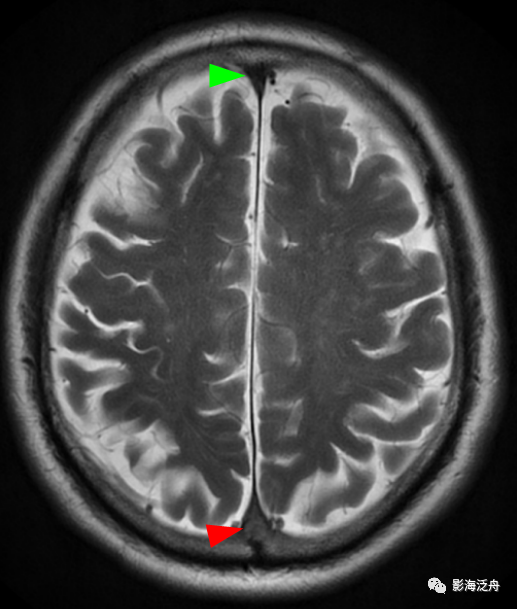

病例三:患者男,67岁,头晕伴头痛1周,既往有脑梗死病史,血压145/95mmHg,神经系统查体无殊。

病例三:静脉窦血栓。正常情况下,上矢状窦在SE序列(T1WI)和FSE(T2WI)序列上均呈流空低信号(绿箭头),本例中上矢状窦呈等高信号(红箭头),结合患者头痛病史,应考虑上矢状窦血栓。